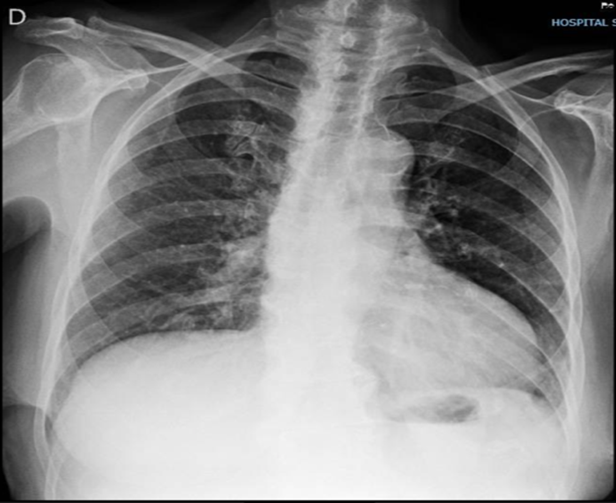

Stanford type A acute aortic dissection associated with aircraft cabin depressurization: cause or coincidence?

Mauer Alexandre da Ascensão Gonçalves, Humberto Morais, Valdano Manuel, Fernando Coelho, Sheila Gonçalves, Fernando Flora

27-29